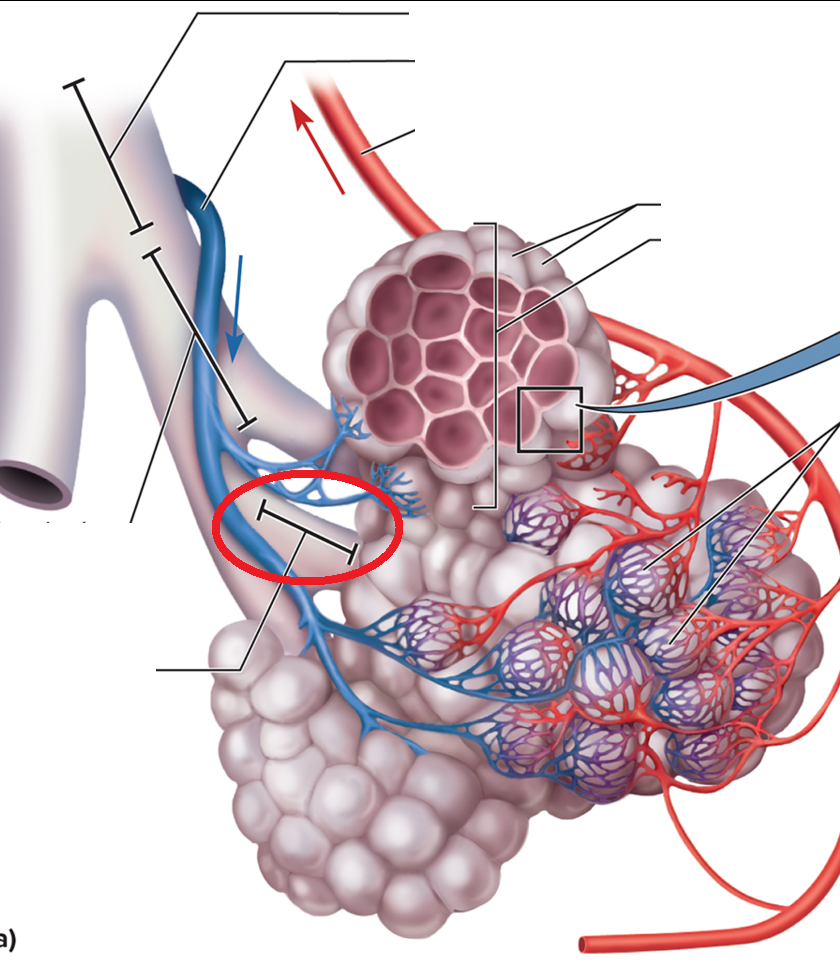

Alveolar duct BT

Alveolar sac BT

Alveolus BT